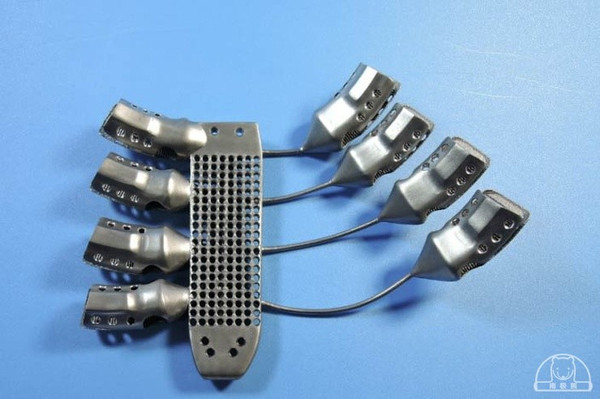

这位病人患有胸壁肉瘤,必须要切除胸骨和一部分的肋骨,然后再以钛金属植入物代替。比起传统方法,3D打印的植入物可以实现完全的定制化,制造速度也更快,而且可以解决现有设计中存在的一些问题。

据了解,此次的手术是由西班牙萨拉曼卡大学医院的团队完成的,所使用的钛金属3D打印植入物则是由澳大利亚的医疗设备公司Anatomics制造的。该公司首先利用从病人身上获取的扫描数据创建了植入物的3D数字模型,然后利用使用澳洲联邦科学与工业研究组织(CSIRO)在今年5月刚刚建立的Lab 22中的Arcam 3D打印机制作出了最终的成品。该设备使用的是电子束熔融技术,能够融化钛金属粉末,然后以层层叠加的方式制造金属物体。